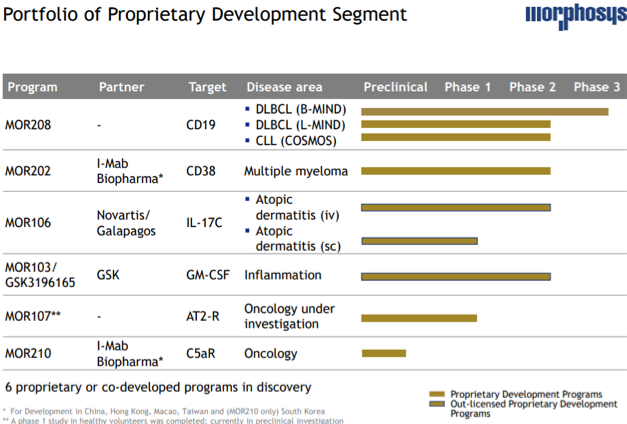

This biotechnology company is a pioneer in field of therapeutic antibodies and has an innovative proprietary technology platform based on antibody capabilities and peptide formats. Its lead product candidate MOR208, a lenalidomide combination in relapsed/refractory diffuse large B cell lymphoma (r/r DLBCL) has been awarded a breakthrough therapy designation by the FDA. The company boasts of a vast pipeline of products consisting of over 29 product candidates by virtue of various proprietary and partnership agreements.

Its proprietary development pipeline consists of its lead product candidate MOR208 targeted at DLBCL (B-MIND) and is in phase III clinical trials, while its MOR107 for oncology is in preclinical stage. It is developing MOR202 for multiple myeloma in partnership with I-Mab Biopharma for development in China, Hong Kong, Macau, Taiwan and South Korea (MOR210 only) and MOR210 for oncology applications, the company has received a $20 million upfront and is eligible for another $100 million in milestone payments and tiered double-digit royalties.

It has collaboration with Novartis (NYSE:NVS)/Galapagos (NASDAQ:GLPG) for development of MOR106 for treatment of atopic dermatitis for which the company has received EUR 95 million and will receive an estimated EUR 850 million in milestone payment in the future along with royalties.

It is also developing MOR103 /GSK3196165, an anti – GM-CSF antibody for inflammatory diseases in a full out-licensed agreement with GSK in lieu of EUR 22.5 million upfront payment and potential milestone payments of EUR 423 million and royalties.